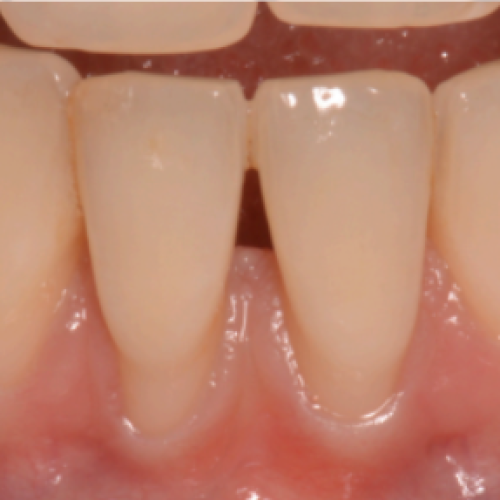

Cirugía periodontal y periimplantaria

Son aquellos actos dedicados a mejorar el pronóstico y facilitar la limpieza y mantenimiento de las piezas que se tratan. Cuando las circunstancias lo permiten existen técnicas y biomateriales para restaurar los tejidos perdidos. Estas maniobras sirven para tratar tanto dientes como implantes.